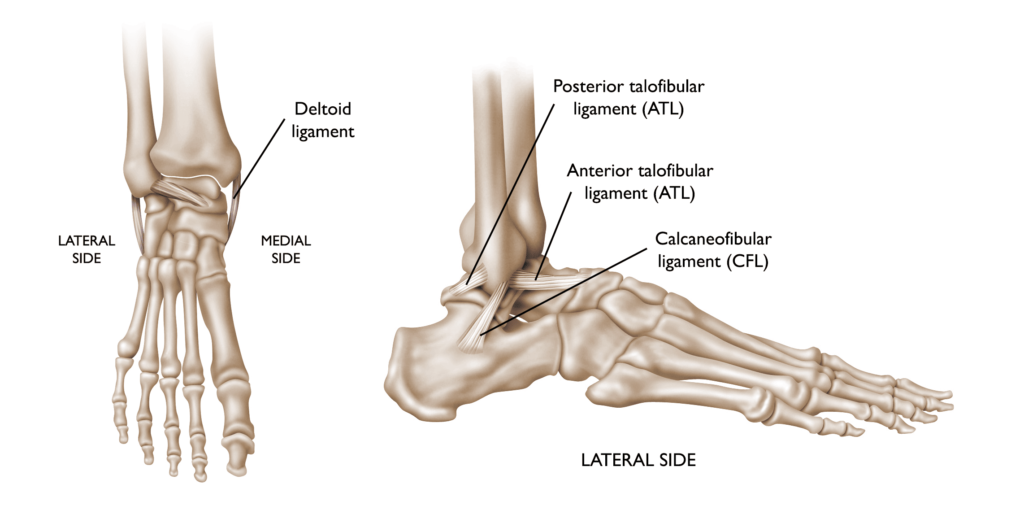

Ligaments are robust, fibrous tissues that play a vital role in connecting bones throughout the body, ensuring stability and proper alignment of joints. In the ankle, multiple ligaments work together to maintain bone positioning and provide the joint stability needed for daily activities like standing, walking, and running. Approximately 90% of ankle sprains result from an inversion injury, where the foot turns inward, primarily affecting the anterior talofibular ligament (ATFL) and the calcaneofibular ligament (CFL) on the outer side of the ankle. Less commonly, medial ankle sprains occur due to eversion injuries, where the foot turns outward, damaging the deltoid ligament on the inner side of the ankle.

An ankle sprain is an injury to one or more of the ligaments that stabilize the ankle.

The lower leg or foot can roll, or invert, leading to a sprain of the ligaments on the outside of the ankle.